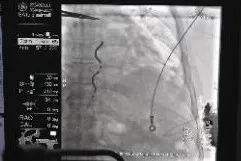

EV-ICD术中测试与术后影像

患者为61岁男性,一年前诊断冠心病并植入三枚支架,入院检查心脏超声EF 31%,动态心电图显示:室性早搏二联律,短阵室性心动过速。诊断为缺血性心肌病,为心脏性猝死的高危患者,术前影像学评估患者解剖适合EV-ICD的植入。 术前,新医大一附院汤宝鹏教授和手术团队与患者及家属进行充分沟通,同时多次与海内外专家、麻醉、医护团队进行了充分细致的案例讨论和手术操作复盘;术中,内外科团队紧密协作,EV-ICD植入手术过程顺利,胸骨下电极稳定,电学参数正常,除颤测试通过。患者于次日转回普通病房,优化各项参数,恢复良好。